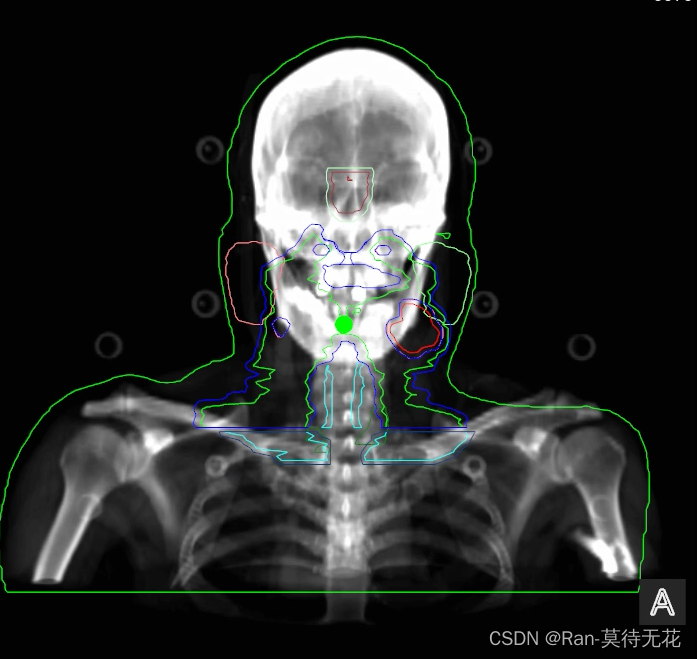

如果需要把结构集数据展示在DRR图像上,只需要用[0,1,0]的法向量旋转一定角度,在计算出新的法向量,用新的法向量切面去切ROI的三维模型即可(生成ROI三维模型的方法在RTSTRUCT ROI三维模型)

最终得到的图像如下: